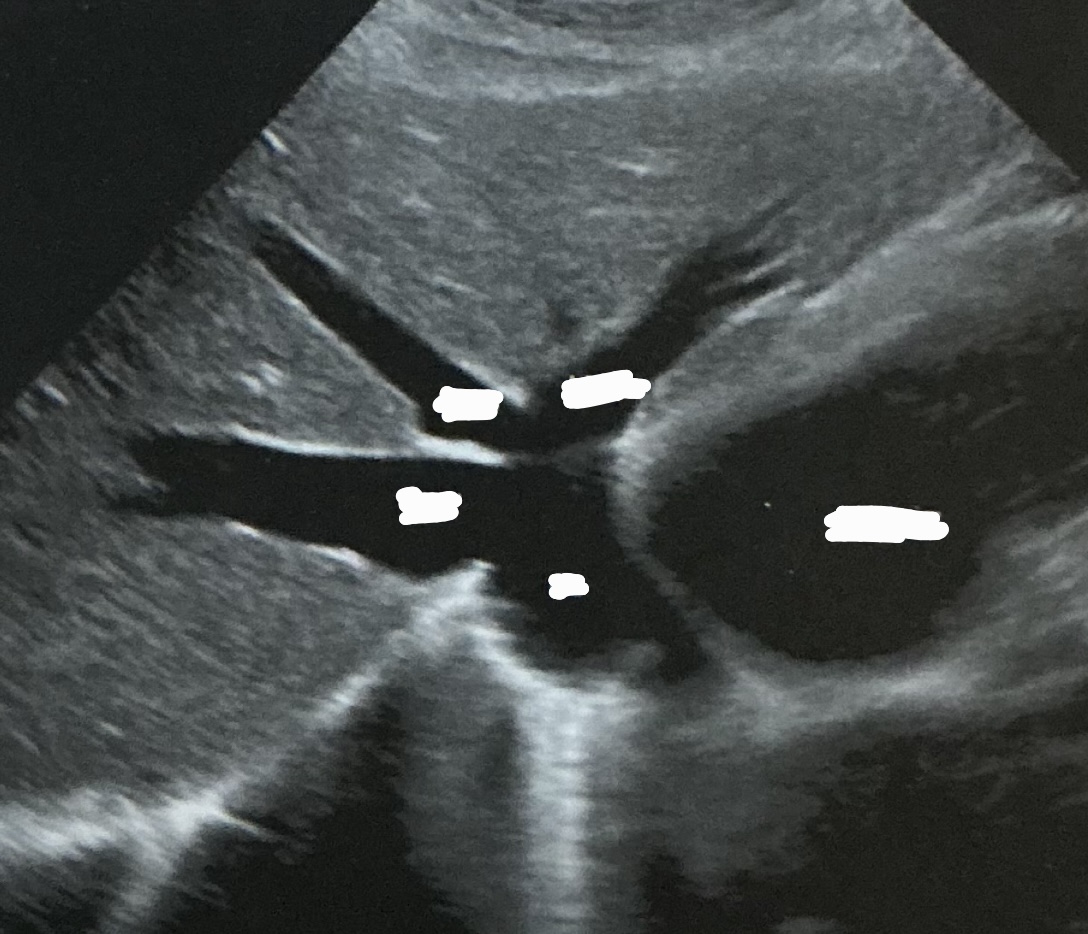

Label this picture

what sign is it depicting

Why does this happen?

What sign does the hepatic veins normally depict?

Canadian moose sign

Dilatation from right heart failure

Playboy bunny sign